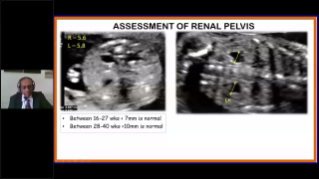

Optimierte OBG-Workflows sind n?tig, wenn gro?e Patientinnenzahlen im Rahmen von Gesundheitsscreenings bew?ltigt werden sollen. Zum Beispiel sind Fehlbildungen des zentralen Nervensystems (ZNS) eine der h?ufigsten angeborenen Anomalien. Wegen verschiedener f├╝r die Bildgebung ung├╝nstiger Bedingungen, etwa eine schwierige Position des F?tus, ist es besonders schwer, die MSP von 2D-Ultraschall zu erhalten. Aus diesem Grund k?nnen automatisierte Erkennung und Messungen die Scanning-Effizienz deutlich steigern.